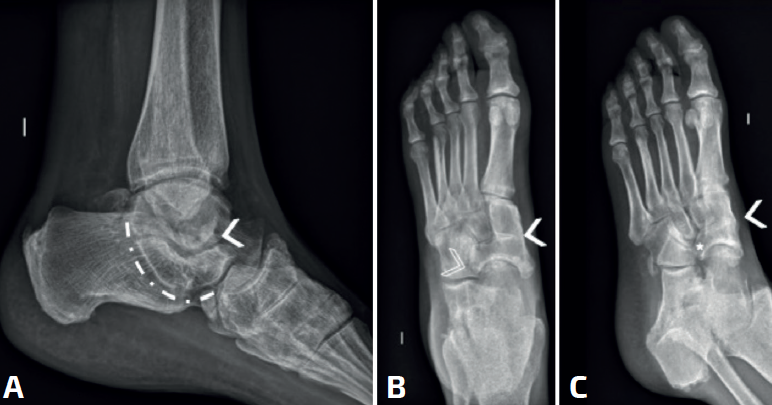

Las radiografías simples deben ser siempre bilaterales. Se deben solicitar: anteroposterior (AP) en carga, lateral en carga y oblicua a 45°. La radiografía a 45° descrita por Sloman en 1921(39) demuestra la presencia de coaliciones CN en el 90-100% de los casos(40,41). Es cierto que la superposición de los huesos del tarso dificulta el diagnóstico de la coalición, pero se han descrito algunos signos distintivos directos e indirectos que ayudan al diagnóstico, siendo los más conocidos el signo del oso hormiguero, el pico del astrágalo (talar beak) y el signo de la C. Estos signos clásicos muestran una buena especificidad, pero una sensibilidad moderada: el hecho de que la coalición sea fibrosa, cartilaginosa u ósea, y el tamaño variable de la coalición influirán en la imagen y en nuestra capacidad de diagnóstico.

El hocico del oso hormiguero es diagnóstico de una coalición CN. Inicialmente descrito en las radiografías oblicuas, también puede ser visible en las proyecciones laterales(37,42,43)(Figura 6A). El proceso anterior del calcáneo normalmente es triangular, pero se alarga en las coaliciones y la punta es cuadrada como el hocico de un oso hormiguero. Un estudio de Crim y Kjeldsberg(22) demostró en radiografías laterales una sensibilidad del 72% y una especificidad del 90% del signo del oso hormiguero, y del 90-100% de los casos en las oblicuas(40,41). Será incompleta en caso de fibrocartilaginosa y completa en las uniones óseas.

El hocico del oso hormiguero inverso: en la radiografía AP en carga del pie, se verá el proceso lateral del escafoides más alargado (Figura 6F, flecha). Normalmente los márgenes están alineados con la cabeza. En las coaliciones, el borde lateral tiende a estar más alargado (Figura 6B, asterisco), en algunos casos su borde es cuadrado y parece articular con el calcáneo. La sensibilidad original reportada de este signo fue del 50% y la especificidad fue del 100%(22), aunque un informe posterior encontró una sensibilidad de tan solo el 18%(44).

El pico del astrágalo (talar beak) se produce secundariamente por la rigidez del retropié(45). La articulación de Chopart aumenta su movilidad a dorsal, el escafoides sube por encima de la cabeza del astrágalo creando con la tracción capsular un pico (es más común en las TC que en las CN) (Figura 7).

El signo de la C o C-sign es el signo directo más fácil de identificar en la vista lateral. Analizando la faceta medial de la articulación subastragalina en las coaliciones TC, que son las más frecuentes (Figuras 7 y 8). Si es distrófico o la línea articular es irregular, sugiere osteoartritis. Los pacientes suelen ser jóvenes al diagnóstico. Posteriormente, en caso de sinostosis con continuidad entre el calcáneo y el astrágalo, un bloque óseo une la voluminosa faceta medial distrófica al sustentaculum tali. Tiene la forma de un arco convexo posteriormente: de ahí el “signo de la C”(45). En pies planos puede ser positivo sin coalición(46) (sensibilidad del 88% y especificidad del 87%)(22).

La ausencia de la faceta medial (subastragalina) precisa de una proyección exacta lateral centrada en el retropié(22). Si la articulación subastragalina posterior es visible y bien alineada, la anterior debiera ser igualmente visible; si no, es posible una coalición(22,47) (sensibilidad del 72-100% y especificidad del 42-94%) (Figura 8A).